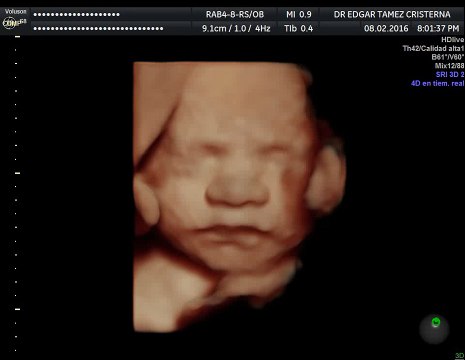

¿En qué ayuda un ultrasonido entre las semanas 11-13.6 del embarazo por un médico materno fetal?